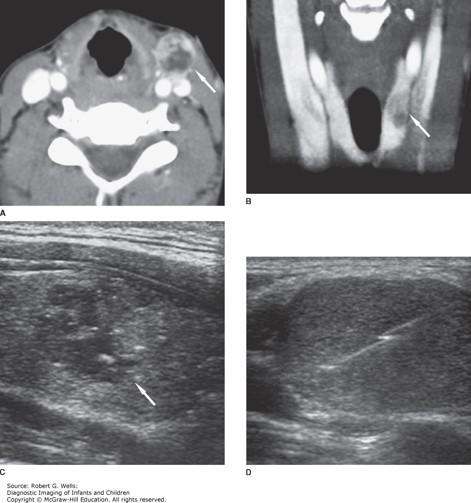

Differentiated thyroid carcinoma (papillary). This 14-year-old girl presented with a palbable left neck mass. A. Axial contrast-enhanced CT at the level of the mass shows an enlarged, heterogeneously enhancing lymph node (arrow). B. The primary tumor is visible on this coronal image as a hypoattenuating lesion (arrow) in the left lobe of the thyroid. C. The nodule (arrow) is predominantly hypoechoic on this longitudinal sonographic image. D. Percutaneous core needle biopsy of the metastatic lymph node provided material for a histological diagnosis.

The correct answer is “C.” The most common presentation of a patient with thyroid cancer is the presence of a solitary thyroid nodule or mass. Although approximately 2% of children have palpable thyroid nodules, most of these are benign adenomas or cystic lesions. Patients with thyroid cancer may have a history of external radiation to the head and neck, exposure to nuclear fallout, a history of rapid growth of the thyroid nodule, a firm or fixed neck mass, hoarseness, dysphagia, or cervical lymphadenopathy. Thyroid cancer is divided into four main types: papillary, follicular, medullary, and anaplastic. In children, the vast majority of masses are differentiated thyroid cancer, which includes both papillary and follicular thyroid carcinomas. Medullary thyroid carcinoma (MTC) is notable due to the production of calcitonin from the parafollicular or C cells of the thyroid gland, and it may be associated with multiple endocrine neoplasia type 2A (MEN 2A) or MEN 2B. Diagnosis of thyroid carcinoma is made by fine needle aspiration biopsy.